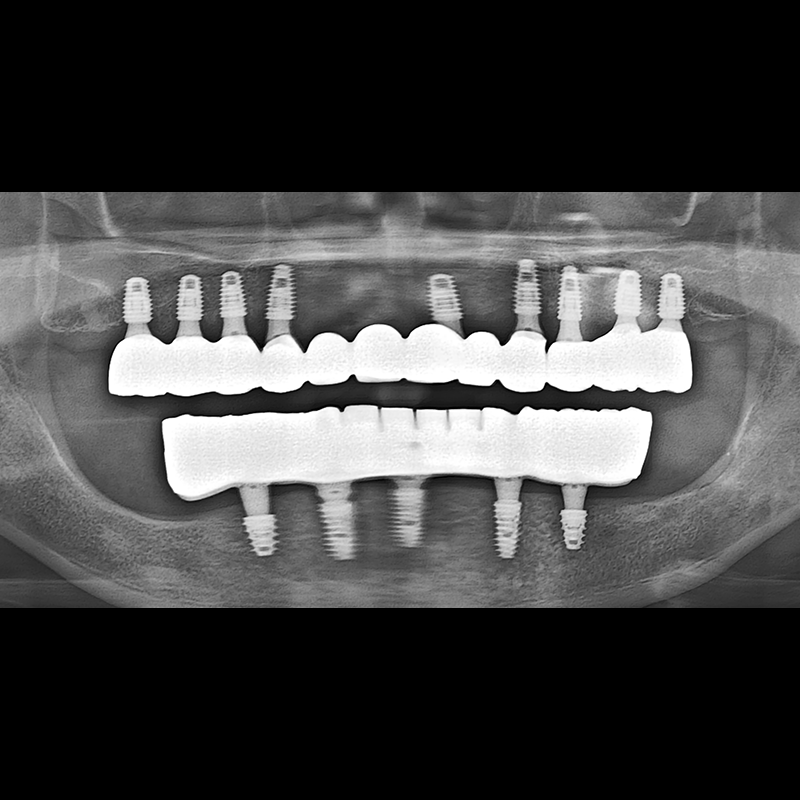

BEFORE AFTER

种植牙前后的照片 2025.05.30

在缺失的牙齿部分和难以挽救的牙齿位置植入了种植牙。